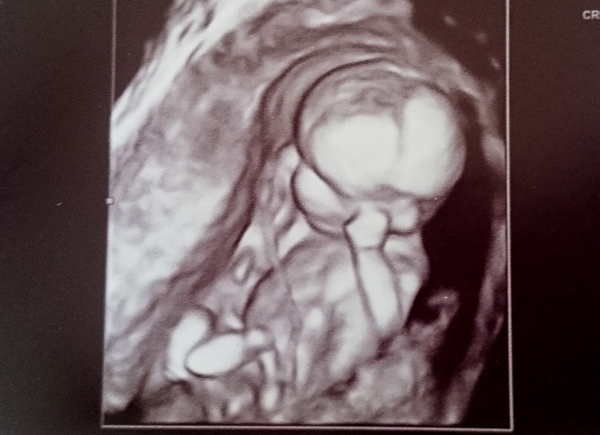

12w1day ..... would love some guesses - 19 week scan on Monday & we have no clues

We had a student sonographer and she wasn't game to figure out how to get the nub shot but we did get a lot of pics because she was training - 64 images in all.

These I think are the best of what we have. We have our next scan at 19weeks, this coming Monday ...hoping we will know the gender for Christmas...

In the meantime is does anyone want to have a guess for us?

I found these paper copies of scans from 11weeks at OB's office ...I don't know nubs from dots and these aren't the clearest pics, but I thought I'd add them while I count the hours and minutes down to scan haha (as far as I know we're not having a unicorn either... though the 2nd picture begs to differ!)... With all this excitement what's the bet we have a shy bump today! An hour and counting!